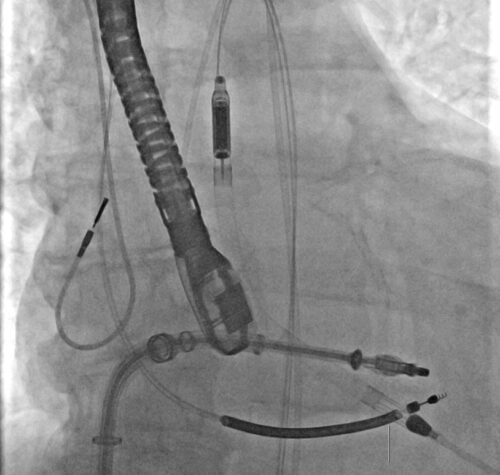

È fuori pericolo un bambino di 9 mesi arrivato in condizioni critiche all’ospedale pediatrico Giovanni XXIII di Bari per una grave insufficienza respiratoria legata a un sospetto caso di botulismo….